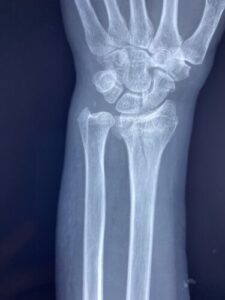

骨折・脱臼

骨折・脱臼に関する研修会の役員をしています。同じ役員の先生方と講師のもと、同業の先生達に向けて骨折・脱臼の治し方の実技指導をしております。

さわやか千葉県民プラザ(前腕骨下端部骨折)